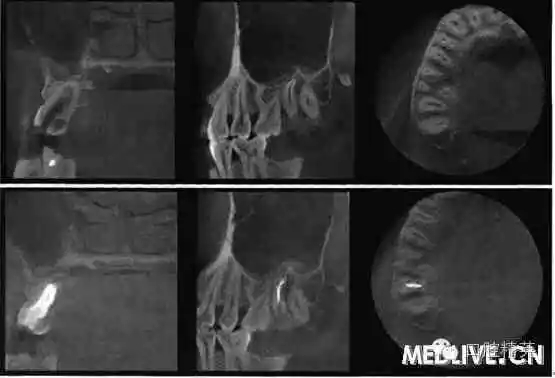

7⊥頜面中央窩見開髓洞型,叩痛(++),無松動(dòng)。X線片示7⊥牙根融合為一彎曲單根,根管粗大,根尖1/3偏向遠(yuǎn)中,無充填物,未見髓室底(圖1上)。錐形束C’r檢查示:根管橫斷面僅見一個(gè)根管口略呈啞鈴形,頰舌向管徑粗大,中下1,3存在牙本質(zhì)島,根尖1,3明顯彎曲偏向遠(yuǎn)中,彎曲角度為34.30(圖2上)。

上:初診:下:根管充填后。

圖2錐形柬CT影像